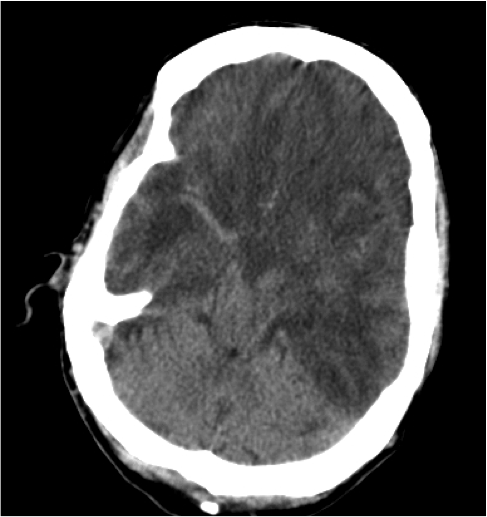

Hemorragia Intraventricular.

- La hemorragia intraventricular se origina por la rotura de las venas subependimarias a lo largo de la superficie de los ventrículos o por extesnión directa de una HSA o de un hematoma parenquimatoso al sistema ventricular.

- Puede ocasionar hidrocefalia.

Hemorragia Subaracnoidea.

- Es la causa + frec de HSA, se observa 40% de los pacientes.

- Se produce por lesión vasos SA o también por extensión directa de contusiones o hematomas intracraneales al espacio subaracnodeo.

- Son líneas hiperdensas a lo largo de los surcos cerebrales, cisura silviana o en cisternas de la base.

- Comparado con la HSA por rotura de aneurisma, la de origen postraumático suelen se de localización periférica, por encima de los hemisferios cerebelosos.